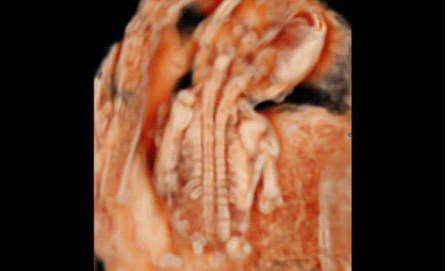

3D/4D成像方面,Hera i 10通過結(jié)合先進的圖像渲染技術(shù),著重加強了邊緣和小結(jié)構(gòu)的可視化能力。